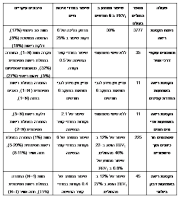

| 08:57, 5 במרץ 2015 | AsthmaCOPD2.jpg (קובץ) |  |

582 קילו־בייטים | Motyk | 1 | |